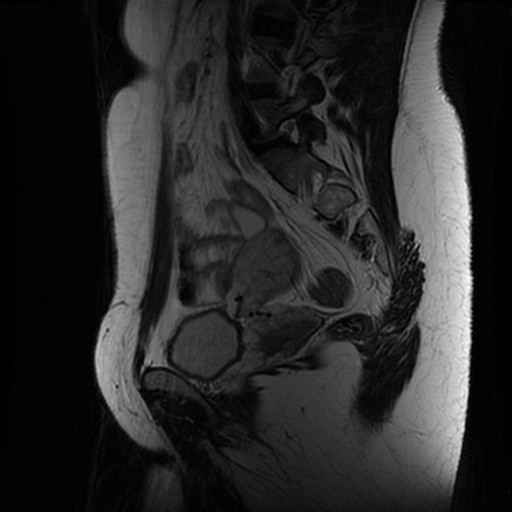

Lage Wervel Zuil